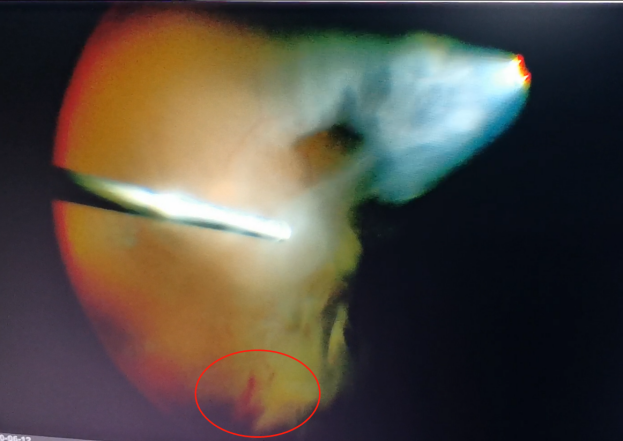

手術(shù)中,醫(yī)生們先后為程先生行白內(nèi)障超聲乳化術(shù)及后入路玻璃體切割術(shù),并置入人工晶體。手術(shù)僅用半個(gè)小時(shí)便順利完成。

(左為玻璃體切割術(shù)中,明顯可見(jiàn)有積血;右為激光治療后的眼底)